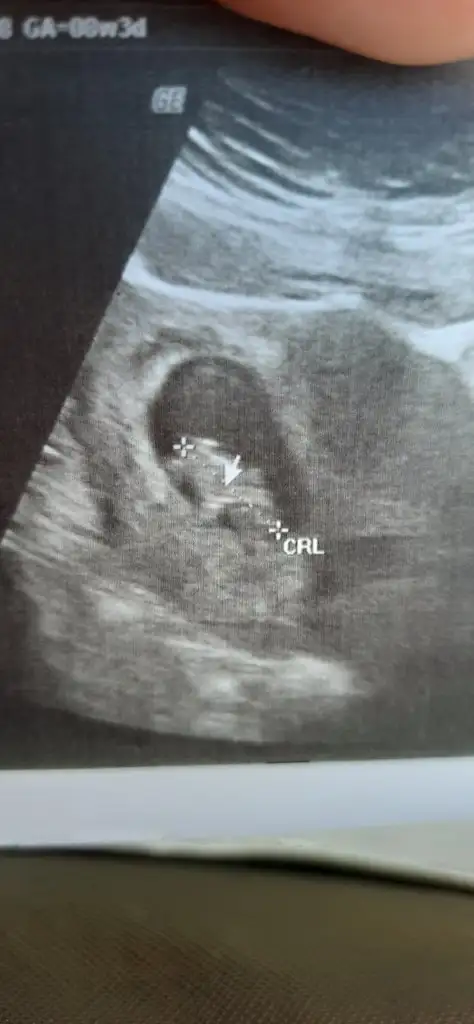

Sağolun teyzeleri iyiymiş şükür hatta ultrasonda bakarken kesenin sağındaydı ortaya doğru devrildi 🤭🤭🤭 1 ay sonra gidicez tekrar :(

Eklentiler

• 20210422_170241.webp

20210422_170241.webp

19,6 KB · Görüntüleme: 51